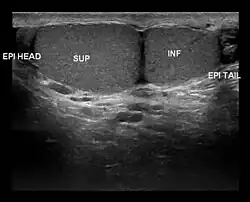

Ultrasound scan showing a side view of Type A3 polyorchidism, with annotations showing the superior and inferior testes and the head and tail of the epididymis

• Type A3: The supernumerary testicle shares the epididymis and the vas deferens of the other testicles.

Type A3 is the most common form of polyorchidism, and types A2 and A3 together account for more than 90% of cases.[3] In 65% of cases, the supernumerary testicle is found in the left scrotal sac.[1]